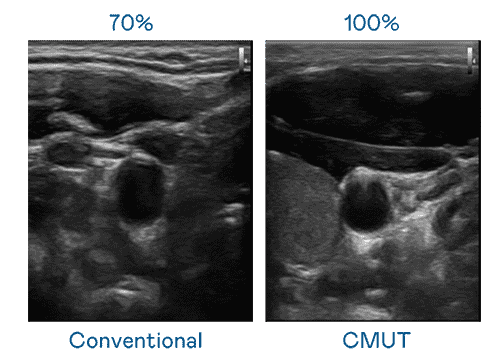

CMUT 技术是一种用电容式微机电元件来产生超音波讯号的技术。。与传统 PZT 压电式技术相比,,CMUT 频宽增加 30%,,,,更宽频的超音波讯号让影像解析度大幅提升,,,,是实现高影像品质医疗超音波扫描、、促进精准医疗发展的关键技术。。

大频宽带来超清晰影像

超音波影像的解析度高低,,首先取决于探头能发出的讯号频宽。。PG国际 CMUT 可提供高清晰的超音波讯号,,,提供高频宽、、高灵敏度、、影像纹理细节更高的超音波影像,,,协助医护人员缩短影像判读时间及利用精准的医疗影像进行诊断。。。